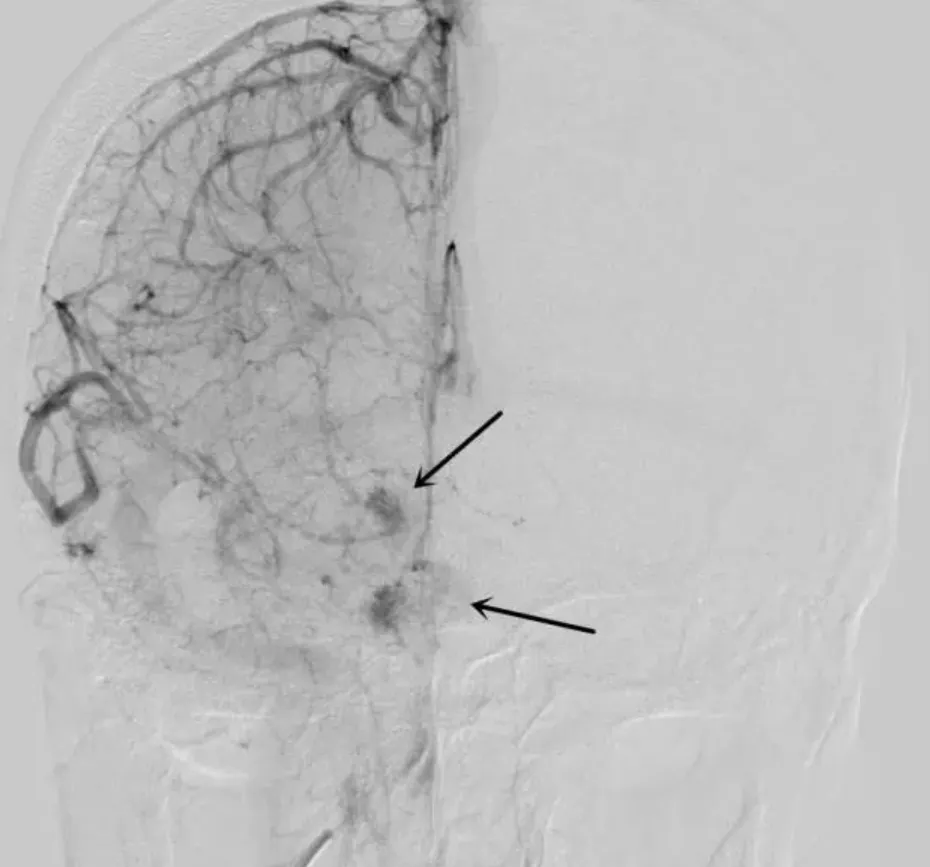

3.脑血管造影(DSA):DSA可以显示血管瘤的血流情况,但对于海绵状血管瘤来说,其诊断价值有限,因为血管瘤内的血流速度较慢。